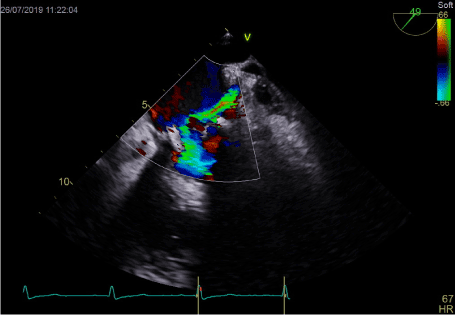

In transthoracic echocardiography we have discovered turbulent flow through mitral prosthesis with no other dysfunction. Appearance and function of aortic bioprosthesis and other heart structures were normal. In transoesophageal imaging there was small thrombus in lateral part of mitral annulus. Patch on left atrial appendage was disrupted and a flow through the leak was visible. This outflow was rapid, turbulent and directed straight to mitral annulus, in close proximity to present thrombus. We suspect mobilization of a thrombus resulting in stroke by rapid left atrial appendage outflow. After the diagnosis of non-obstructive prosthetic thrombosis anticoagulation with low molecular heparin was implemented. In control echocardiography thirteen days later, we have confirmed previously diagnosed thrombus and four new mobile thrombi present. Our next decision was to implement vitamin K antagonist (VKA) with rigid INR control. After two weeks of the VKA therapy we have observed resolution of annulus thrombosis. We plan to continue VKA with target INR 3,0 together with low dose of acetylsalicylic acid for three months and continue further anticoagulation with VKA alone.

Figure 1. Thrombus on mitral annulus and gap in LAA patch

Figure 3. Turbulent LAA outflow directing to mitral annulus